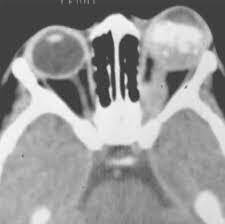

¿Cuáles son los hallazgos radiológicos en la TC del exoftalmos?

¿Qué es la disociación índice globo ocular?

Es la diferencia en la distancia del ojo izquierdo con el derecho